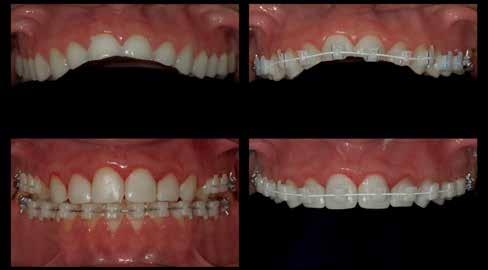

Esetbemutatás

2015-ben egy 47 éves férfi páciens állkapocs-ízületi panaszai miatt kereste fel a rendelőnket. Ezen felül esztétikai problémát jelentett számára, hogy az egyik felső nagymetszőfogán lévő héj eltört (1-3. ábrák). A klinikai és radiológiai vizsgálatot követően megállapítható volt, hogy a páciens kifejezett bruxizmusa miatt csökkent a harapási magassága, és jelentős mennyiségű saját foganyagot abradált el (4. ábra)

Szájterpesz használata mellett digitálisan intraorális fotók készültek a páciensről mind frontális, mind laterális és okkluzális irányokból. További fotók is készültek a páciensről egy digitális tükörreflexes kamera segítségével (frontális és laterális irányból, valamint 45 o-os szögből). Mindkét állcsontról digitális lenyomat készült egy intraorális szkenner segítségével (Care stream 3500). A maximális-interkuszpidációs helyzetet (IKP) szintén a Carestream 3500-as készülék felhasználásával rögzítet -

tük. Az új harapási magasságot a CAD/CAM szoftverben létrehozott virtuális artikulátor általunk meghatározott mértékig történő nyitásával határoztuk meg.

A kiindulási helyzet rögzítésére a DSD dinamikus dokumentáció protokollját használtuk. Egy okostelefon segítségével 4 különböző szögből videókat készítettünk, hogy később ezek alapján ki tudjuk alakítani a páciens legoptimálisabb mosolyát. A következő felvételek készültek: frontális irányú a mosolygó páciensről az ajkak és az orca eltartásával, majd az eltartásuk nélkül, továbbá oldalirányú felvétel, egy a homloktól az állcsúcs irányába mutató, és egy az okklúziós síkra merőleges irányból készült, illetve egy záró harapási helyzetben lévő hátsó fogakról (tükör nélkül).

Négy kiegészítő felvétel készült az esztétikai, a funkcionális és az anatómiai kiértékeléshez: egy videó arról, ahogy a páciens leírja az általa elérni kívánt állapotot, egy 180 o-ban, beszéd közben készült felvétel, egy funkcionális elmozdulásokról készült intraorális videó, továbbá egy ajak és orca eltartása mellett készült intraorális felvétel a szájüregben található anatómiai struktúrákról (5. ábra) . Az így nyert adatokat továbbítottuk a DSD-t készítő laboratóriumnak. A DSD technika célja, hogy kombinálja a három különböző irányból készült felvételt (frontális, oldalirányú és fentről lefele mutató)

A páciens harapási magassága az új minta alapján megemelésre került. A páciens két héten keresztül viselte az általunk elkészített mock-upot, hogy ki tudjuk értékelni a harapásemelés objektív és szubjektív hatásait. Ez alatt az idő alatt a páciensnek lehetősége volt eldönteni, hogy az új harapási magasság megfelel-e az ő elvárásainak. Az ideiglenes felépítés viselése során a páciens jónak ítélte meg az új okklúzióját, és elégedett volt a kapott eredménnyel. Ezért nem volt szükséges a habituális okklúziós helyzet további megváltoztatására és új centrális okklúziós helyzet kialakítására. A páciens megfelelőnek találta az újonnan kialakított harapási magasságát, továbbá nem érzett temporomandibuláris ízületi fájdalmat.

A páciens a megkezdett kezelések folytatása miatt 2017ben ismét felkereste a rendelőnket (7. ábra). Ekkor egy új intraorális lenyomatvétel történt (Carestream 3600).

A fogak preparálásához egy új mock-upot készítettünk háromdimenziós nyomtató segítségével (SolFlex, VOCO) bisz-akrilátból (Structur 3). A mock-up elkészítéséhez felhasznált sablont vákuum technológia segítségével hoztuk létre (V-Print ortho, VOCO). A mock-up felhelyezését követően a páciens fogait minimál invazív módon készítettük elő (8. ábra).

A már előzetesen preparált felső frontfogak csiszolt csonkjainak megtartottuk az eredeti formáját. Az alsó és felső őrlőfogak preparációja nem volt szükséges (1.7-1.4, 2.4-2.7, 3.7-3.4, 4.4-4.7), az alsó kismetsző fogakat minimál invazív módon készítettük elő. Az előkészítést követően új digitális lenyomat készült. Az így kapott digitális adatokat továbbítottuk a fogtechnikai laboratóriumba (9. ábra). A virtuális modellt ezek alapján hozták létre (AnatomicLab), és a minta elkészítéséhez szükséges STL fájlt továbbították egy háromdimenziós nyomtatóra (SolFlex 650, VOCO), amely segítségével elkészítették az új mintát (V-Print model, VOCO).

A végső restaurátumokat (héjakat és koronákat) Ce-

ramill Mind tervező program segítségével (AmannGirrbach) digitálisan megtervezték, majd frézgép segítségével (CeramillMotion 2, AmannGirrbach) li thium-diszilikát tömbökből (VITABLOCS TriLuxe forte for CeramillMotion 2, AmannGirrbach) kifaragták (10. ábra). Miután a fogpróba során ellenőrizték és megfelelőnek találták a pótlások széli záródásának a pontosságát, valamint az elkészült restaurátumok esztétikai megjelenését, ezután egy ajak- és szájterpesz került felhelyezésre (OptraGate, IvoclarVivadent).

A koronákat (1.3-1.1 és 2.1-2.3) és a héjakat (1.7-1.4, 2.4–2.7, 3.7-3.1, 4.1–4.7) fényrekötő adhezív rendszerrel rögzítették a pillérfogakhoz (Futurabond U ésBifix QM, VOCO). A polimerizációhoz egy nagy teljesítményű LED polimerizációs lámpát használtak (Celalux 3, VOCO), (1112. ábrák).

A kifolyó ragasztóanyagot ezt követően eltávolították, majd az okklúziót a T-Scantechnológia (Tekscan) segítségével ellenőrizték, majd a szükséges mértékben korrigálták. A véglegesen rögzített kerámiapótlás védelme érdekében a páciensnek a továbbiakban egy kivehető, átlátszó műanyag fogvédő sínt kellett viselnie. A pótlásokat 6 hónap múlva ellenőrizték. Az át adott fogpótlások stabilan rögzültek, és nem találtunk sérülésekre, repedésekre utaló jeleket (13-15. ábrák). A páciens arról is beszámolt, hogy a harapás megemelése óta megszűntek az őt rendszeresen gyötrő fejfájásai.